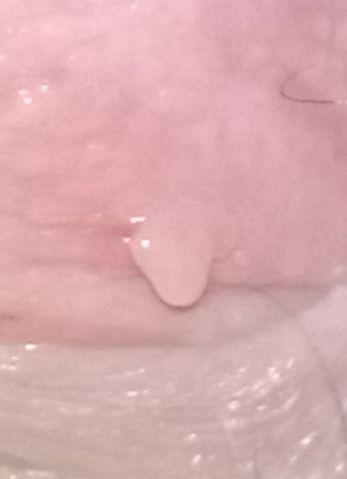

Câu hỏi về vấn đề nhú bất thường ở vùng kín của khách hàng ẩn danh trên group HỎI ĐÁP BỆNH PHỤ KHOA vào ngày 15/4/2026.